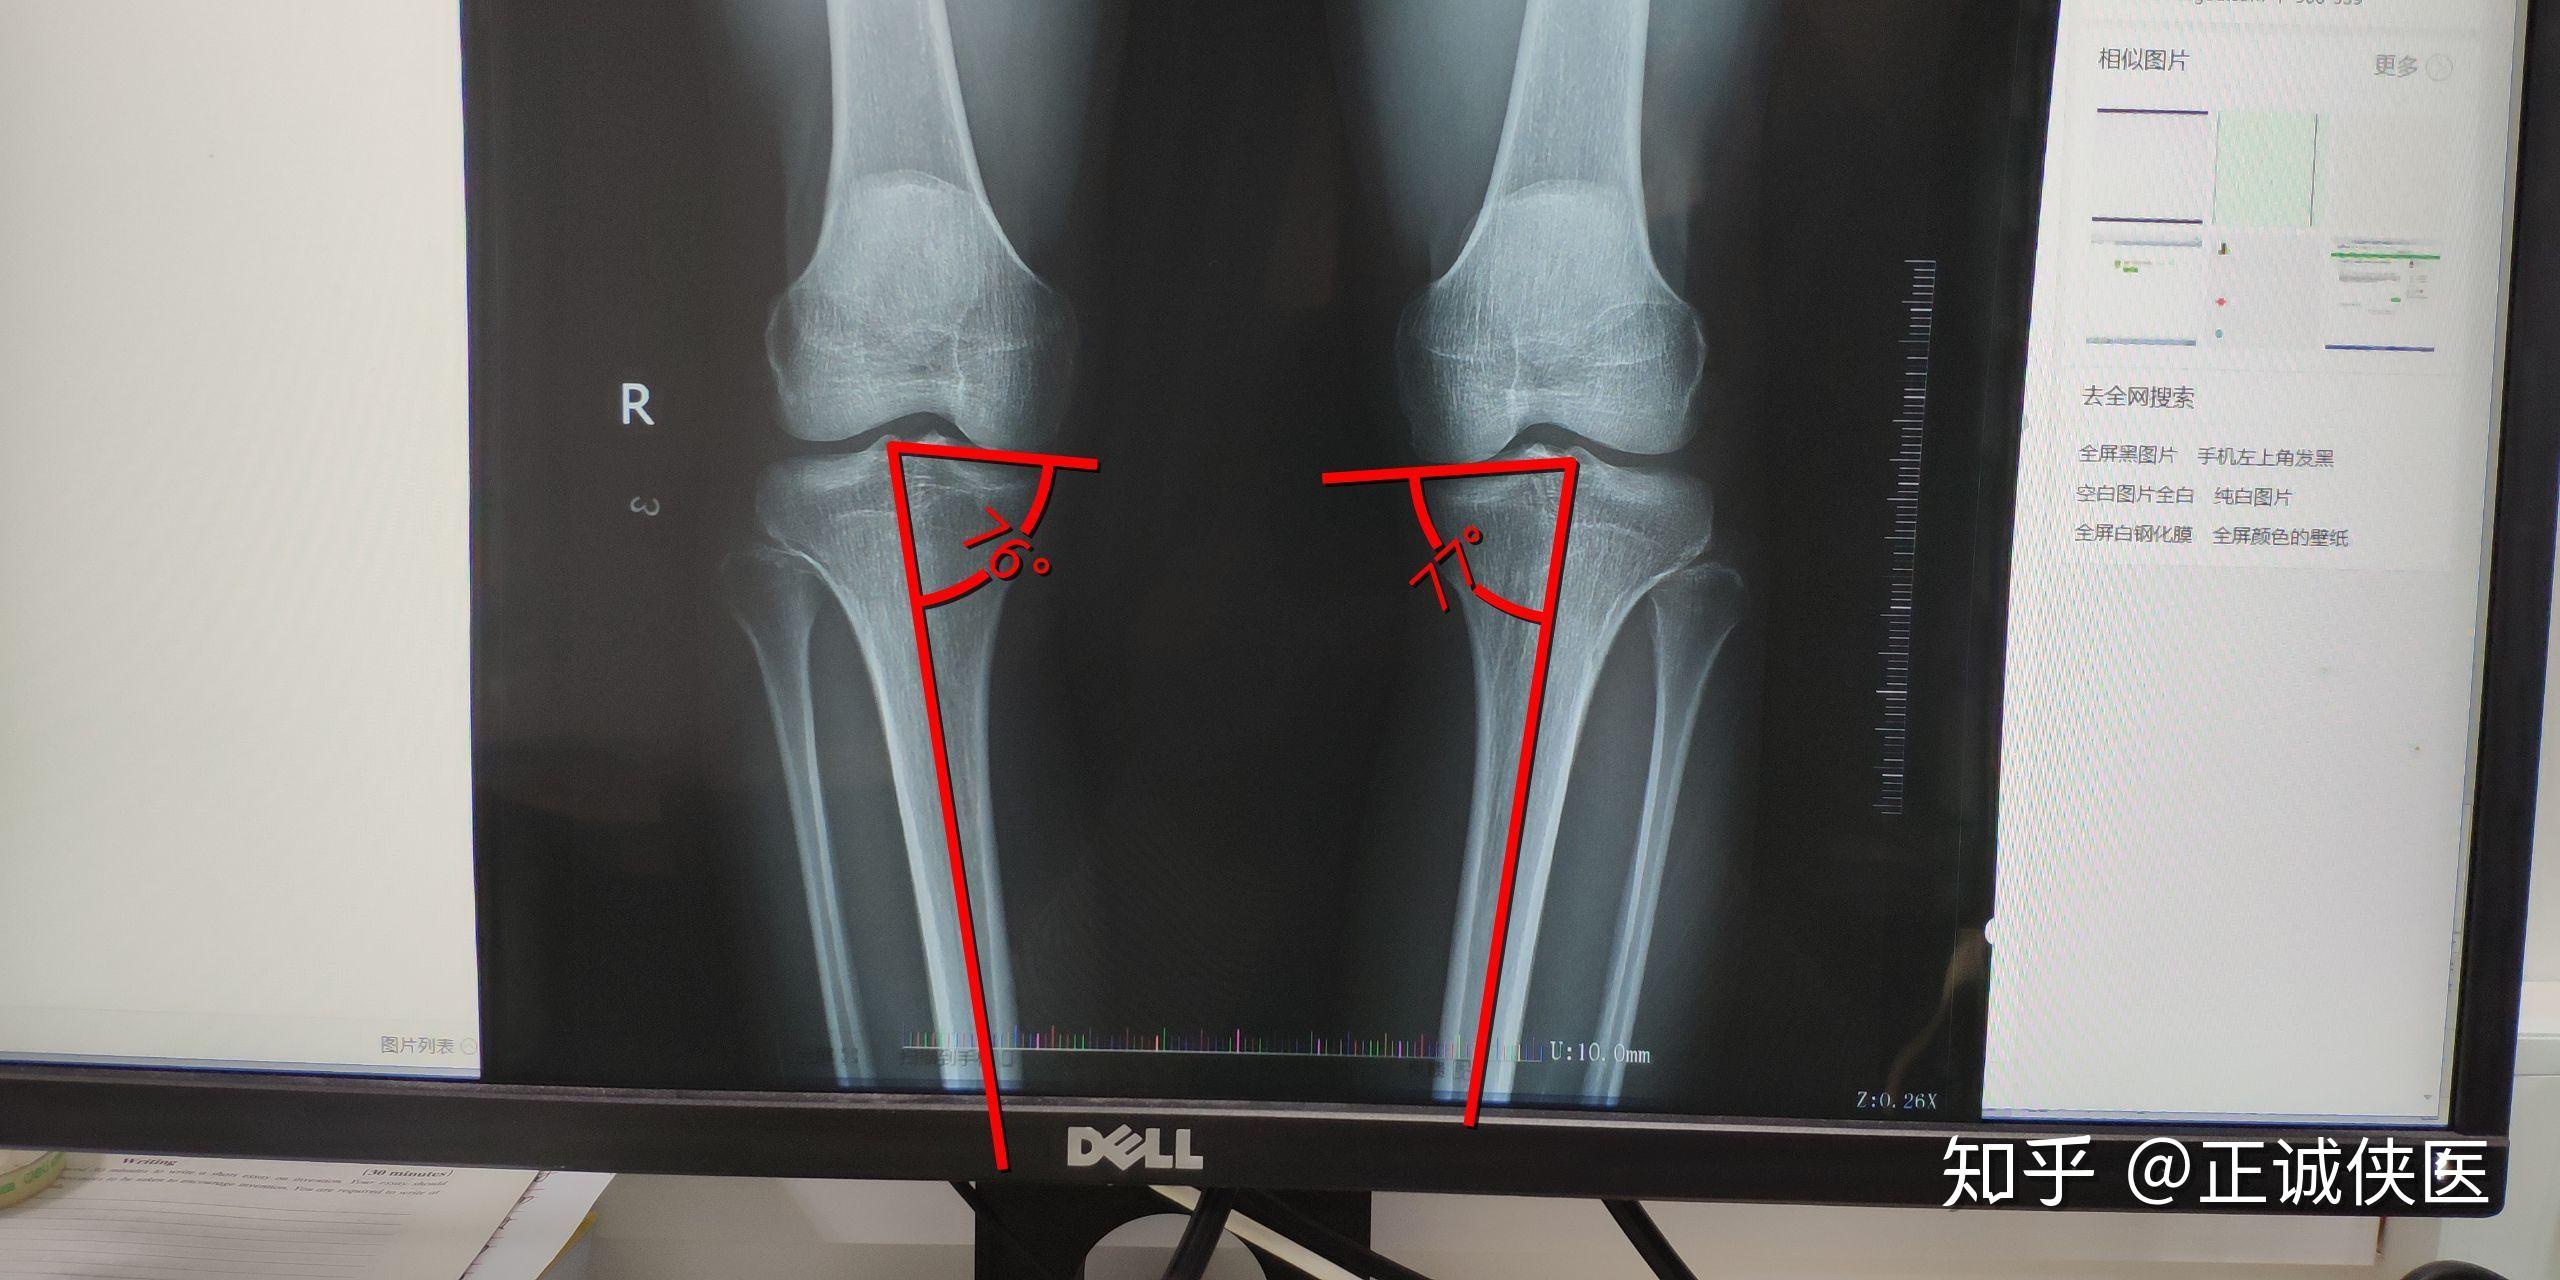

请问一下从x光片上看我的o型腿是关节畸形导致的还是肌肉力量问题啊

o型腿的救星:胫骨外翻截骨术—上海六院保肢专家文根